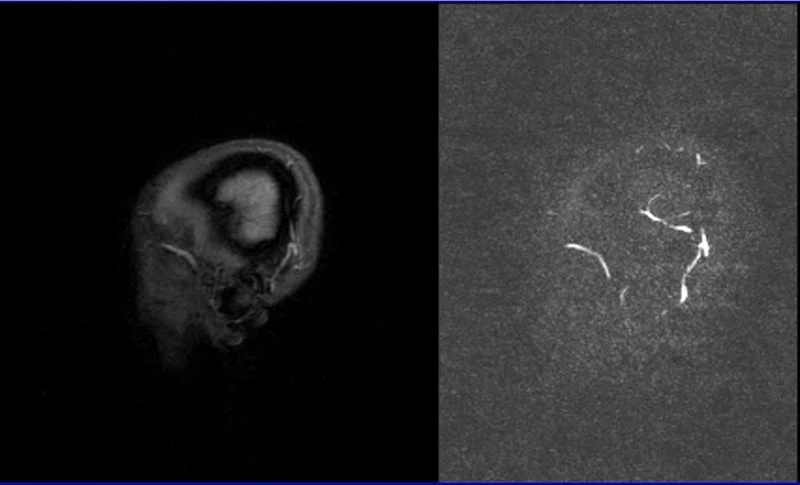

MRV brain phase contrast(PC) 3D images

Post processed MIP images from 3D rowdata